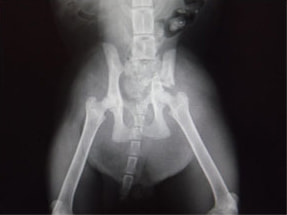

症例:交通事故による椎体脱臼

柴犬:9歳、避妊雌

交通事故直後、胸腰部に激しい疼痛、両後肢に完全麻痺を認め、シェフシェリントン徴候を呈していました。レントゲン検査において、第11-12胸椎間の脱臼が認められました。

脊髄の減圧、脊柱管の再構築・安定化を目的に、片側椎弓切除術およびMatrixMANDIBLE Plateによる椎体固定を実施しました。

隣接椎体を架橋するようにプレートを設置しました。

術後レントゲン写真